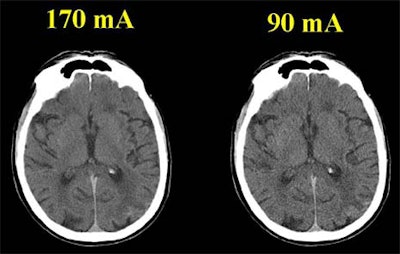

All of the patients underwent conventional non-contrast head CT using a standard multidetector-row technique (LightSpeed premium multislice scanner, GE Medical Systems, Waukesha, WI). The protocol (170 mA, 140 kV, pitch 3, table speed 7.5 mm/sec.) yielded a radiation dose of approximately 65 mGy (6.5 rad).

Having offered their informed consent, the patients then underwent a second scan comprising four additional sections. The protocol was identical to that of the first scan except for the mA, which was nearly halved to 90. Dose being proportional to mA, the effective dose was also nearly halved, Bove said.

In the visual analysis, the low-dose images showed "an increase in modeling, and we can also see that the sharpness is not quite as good. You can see that the margins aren't quite as sharp," Bove said.

Yet most structures remained well defined, and no images were non-diagnostic, he said. The gray matter was not significantly less conspicuous in the half-dose (0.41 ± 0.03) vs. the normal-dose (0.39 ± 0.19) images (p=0.32).

quality remains acceptable for most applications. Image courtesy of Dr. Peter Bove.

As for the signal-to-noise ratio, noise increased by approximately 22% in the half-dose images (1.39 ± 0.38) compared to the normal-dose images (0.39 ± 0.19) (p=0.32). Subjectively, the overall image quality "is only considered slightly less ... than 170 mA, which is the standard," Bove said.